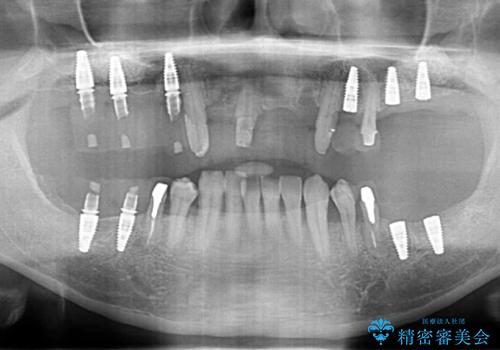

インプラント・ブリッジ補綴を含む、歯周病全顎治療

- 歯が全体的に揺れ始め、恐怖を感じ他院に相談に行ったところ、全体的な歯周病の問題・抜歯の必要性・入れ歯の提案を受け、入れ歯以外の選択肢を希望され来院されました。

全体的な歯周病検査を行い、多数の残すことのできない抜歯の必要な歯を認めたため、残せる歯に対しての徹底的な歯周病治療、失った歯に対しブリッジ・インプラント治療を全顎的に行っていくこととしました。